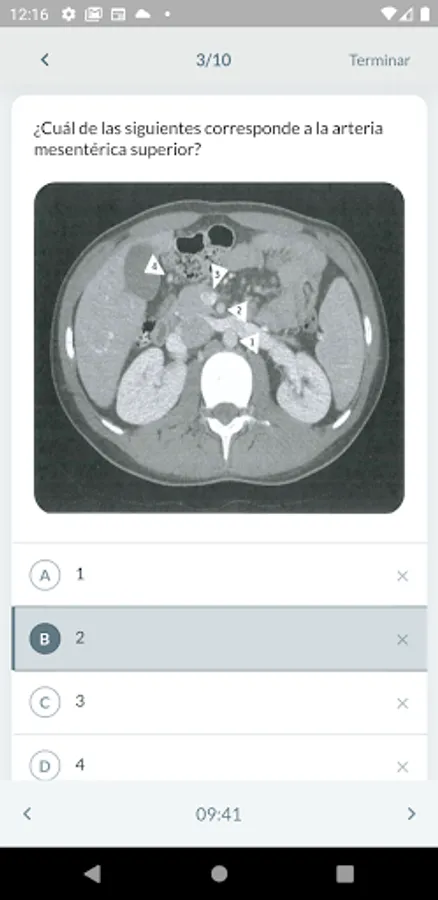

Desgloses Screenshots